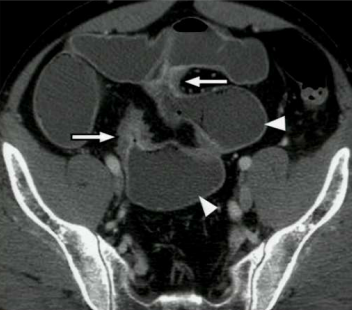

What sign is this?

Rigler sign, air on the inside and outside of the body, indicating pneumoperitoneum.